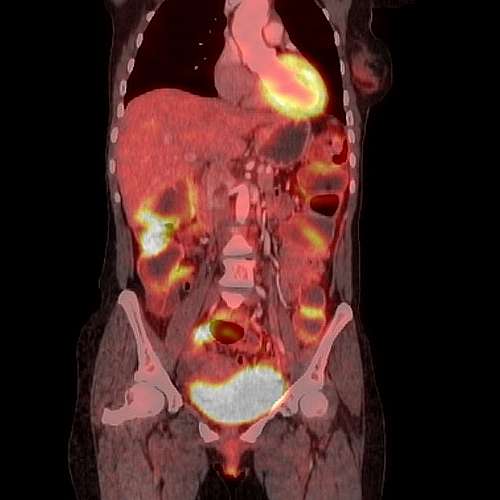

We have a huge number of cases with different modalities and regions

By Modality

By Region